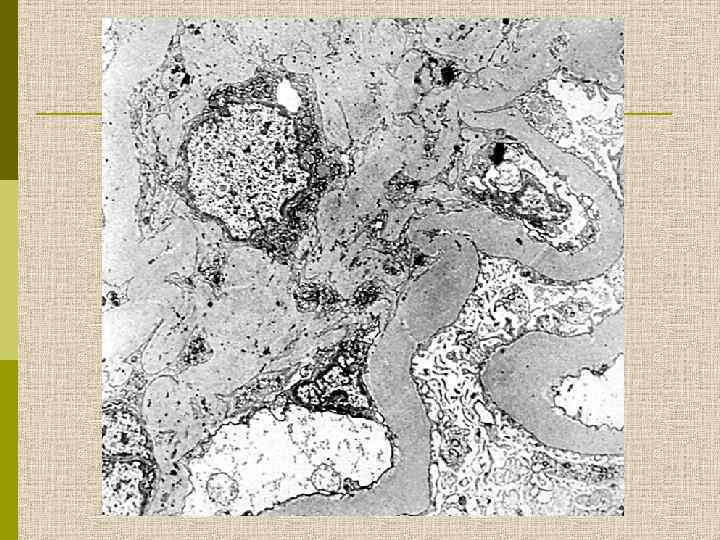

МОРФОЛОГИЧЕСКИЕ ИЗМЕНЕНИЯ ПРИ ДИАБЕТИЧЕСКОЙ НЕФРОПАТИИ Основные варианты - диабетический гломерулосклероз с узелками Kimmelstiel-Wilson - диффузный мезангиальный гломерулосклероз Характерные признаки Утолщение ГБМ; артериолярный гиалиноз; аневризматические капилляры; капсулярные капли; фибриновые шапочки; атрофия канальцев; инфильтрация, расширение и склероз интерстиция; линейные отложения иммуноглобулинов

Узелковый гломерулосклероз (болезнь Киммельстиля. Вильсона). Узелки pink гиалинового материала в области петель клубочковых капилляров – значительное уширение мезангиального матрикса в резельтате неэнзиматического гликозилирования протеинов.